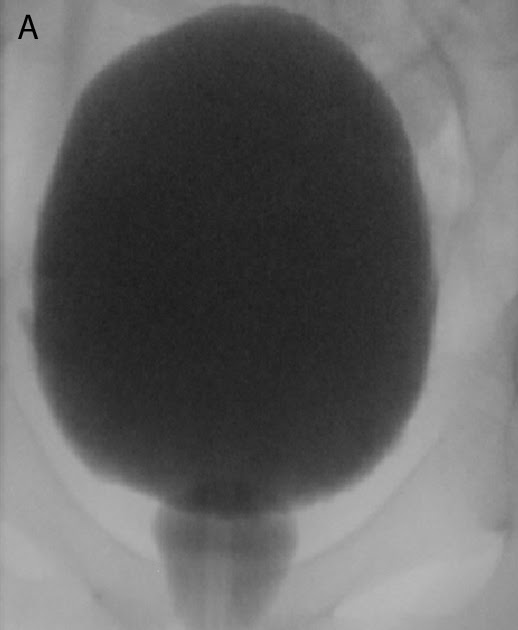

What Is Spinning Top Urethra . spinning top urethra (stu) is a term used to describe a widened posterior urethra seen mainly in girls. spinning top urethra (stu) is a term used to describe a widened posterior urethra seen mainly in girls. spinning top urethra is a rare deformity, characterised by dilated posterior urethra, more common in young women. It is commonly regarded as. the more common outlet dysfunction is the spinning top urethra. It is seen on vcug as a narrowing of the. spinning top urethra (stu) is a term used to describe a widened posterior urethra seen mainly in girls. It is commonly regarded as. It is commonly regarded as. an anteroposterior image from the voiding phase shows focal dilatation of the posterior urethra between the internal. 2b) , characterized by dilation of the. a spinning top urethra seen on voiding cystograms is diagnostic for dv (fig.

Spinning top urethra in a 14yearold girl with daytime wetting What Is Spinning Top Urethra spinning top urethra is a rare deformity, characterised by dilated posterior urethra, more common in young women. It is seen on vcug as a narrowing of the. 2b) , characterized by dilation of the. an anteroposterior image from the voiding phase shows focal dilatation of the posterior urethra between the internal. It is commonly regarded as. It is. What Is Spinning Top Urethra.